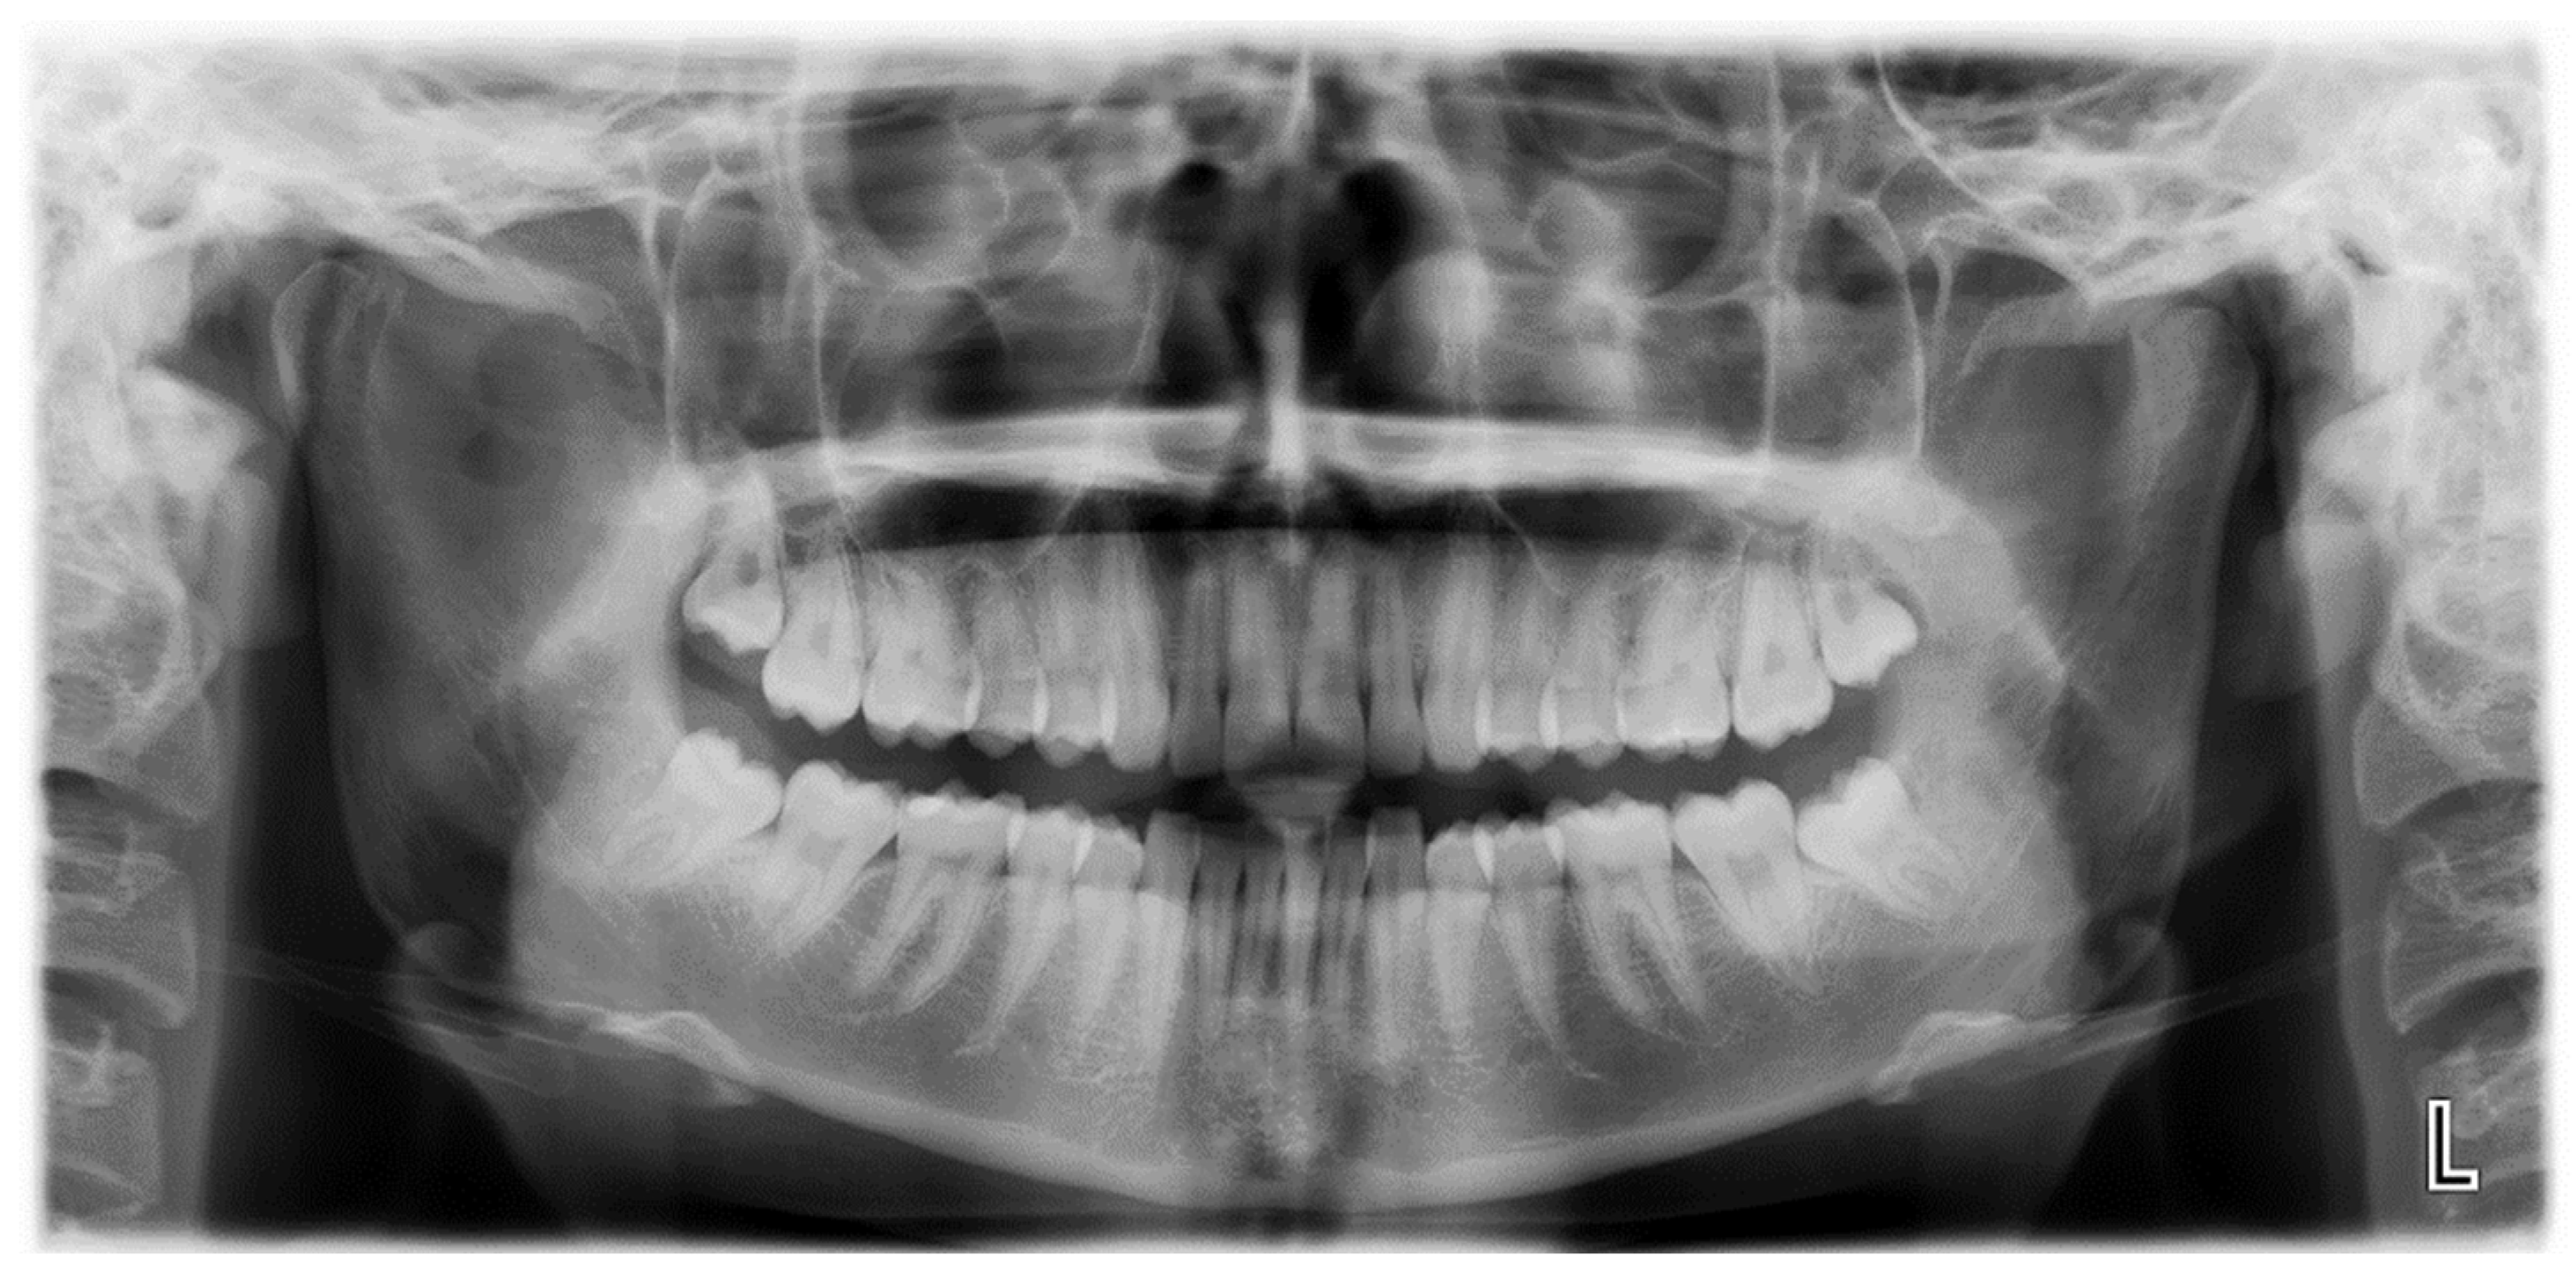

Figure 2.

Cinematic 3D reconstruction (Mimics, Materialise NV, Leuven, Belgium) showing the pseudojoint established between the altered right CPM and the inner aspect of zygomatic bone.